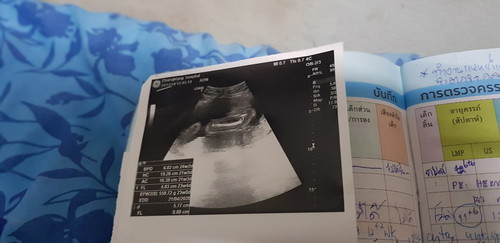

23week??

แม่ๆพอจะดูออกไหมค่ะว่าเพศหญิง/ชาย

หมอว่าไงบ้างค่ะ ภาพไกลมองไม่ชัดจ้า